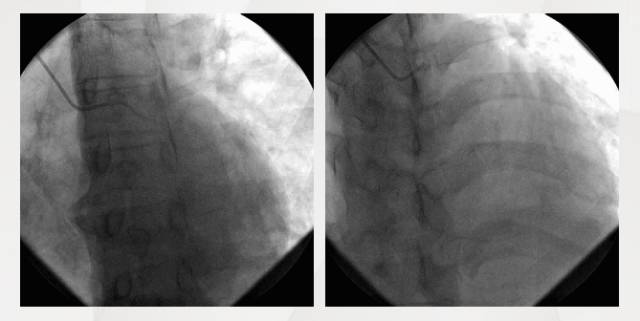

CAG

CAG排除ACS